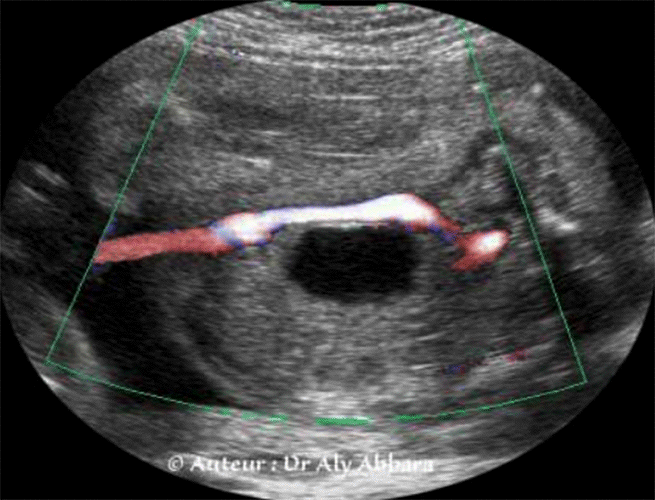

Images échographiqiues mettant en évidence la présence d'une artère ombilicale unique à comparer à la présence des deux artères ombilicales

L'aspect échographique et l'apport du Doppler dans le diagnostic de l'artère ombilicale unique

Série de coupes axiales centrées sur la vessie et montrant le trajet habituel des deux artères ombilicales (branches des artères iliaques internes) qui encerclent la vessie latéralement, puis elles rejoignent le cordon ombilical au niveau de l'ombilic.

Cette coupe permet de diagnostiquer facilement la présence de l'artère ombilicale unique et de déterminer le côté dans lequel l'artère ombilicale est manquante.

Le diagnostic échographique est possible par la réalisation d'une coupe transversale sur le cordon ; l'utilisation du Doppler couleur facilite ce diagnostic. Pour déterminer le côté de l'artère absente, il faut réaliser une coupe transversale au niveau de la vessie, sur cette coupe, le Doppler couleur met en évidence l'artère ombilicale manquante.